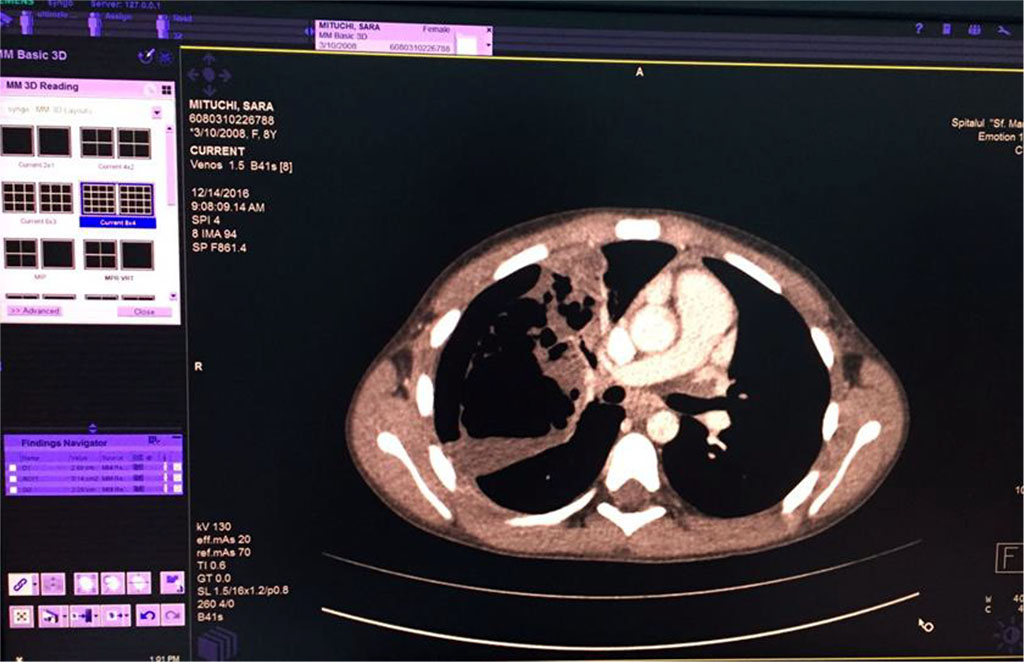

We’ve started the treatment with Ceftriaxone and Gentamicin with unfavorable evolution, increasing chest pain and dyspnea. Our second option was an association between Piperacillin/ Tazobactam without improvement of general state and maintaining of abnormal blood tests. Therefore, thoracic computed tomography was performed (Fig 5,6,7). It revealed the presence of right Pyo-pneumothorax. In that case a pleural drainage was performed in association with large spectrum antibiotic therapy (Meropenem, Linezolid, Metronidazole).

Fig. 6 Air bubbles within the fluid colection of the right lung

Fig. 7. Pulmonary consolidation, inhomogenous, with multiple aeric cysts with sizes from 11mm to 42.3mm